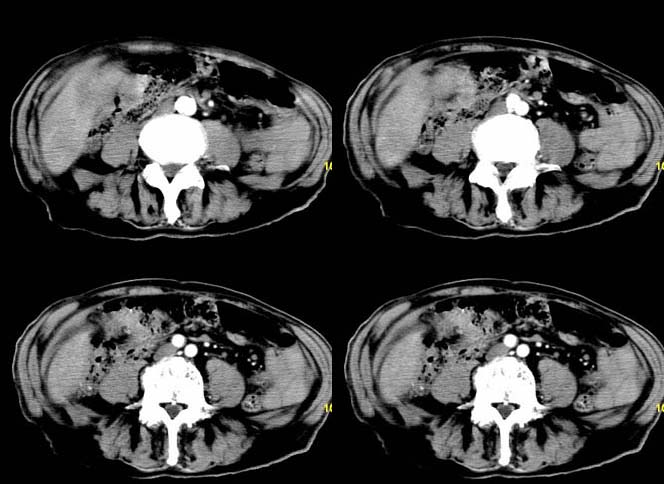

以下是引用余辉在2007-12-6 22:23:00的发言:[br]胆囊内多枚结石影,胆管全程扩张,右肝内病灶强化符合脓肿表现现(左肝病灶图像未传完),考虑急性梗阻性化脓性胆囊胆管炎合并肝多发脓肿(建议补传左肝病灶图像)